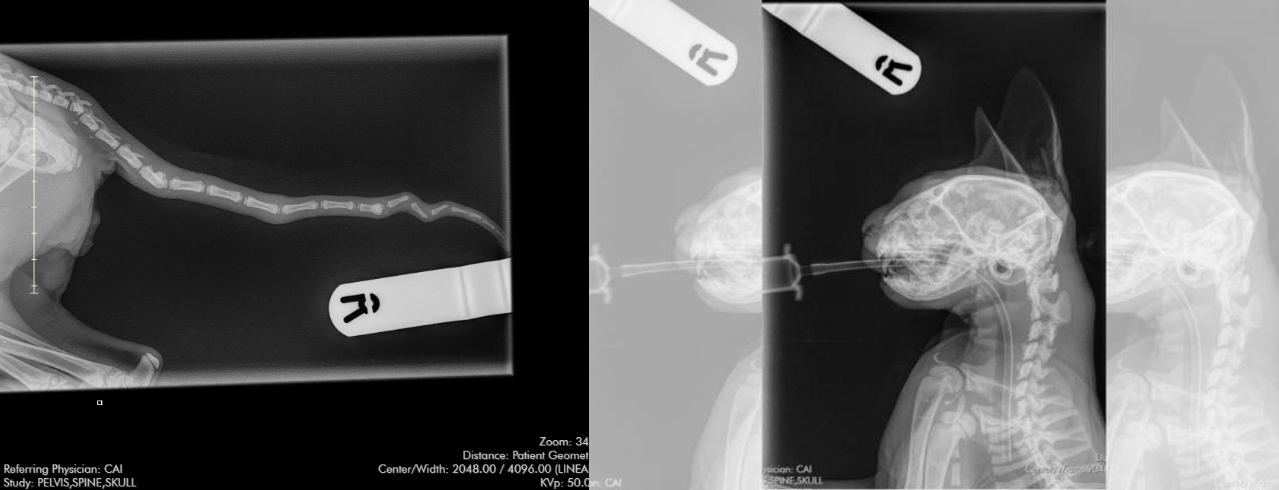

Emaciated Greyhound Found Near Burton in Critical Condition

A severely injured female greyhound has been rescued near Burton, with Greenacres Rescue centre seeking information about her origins while providing emergency care.